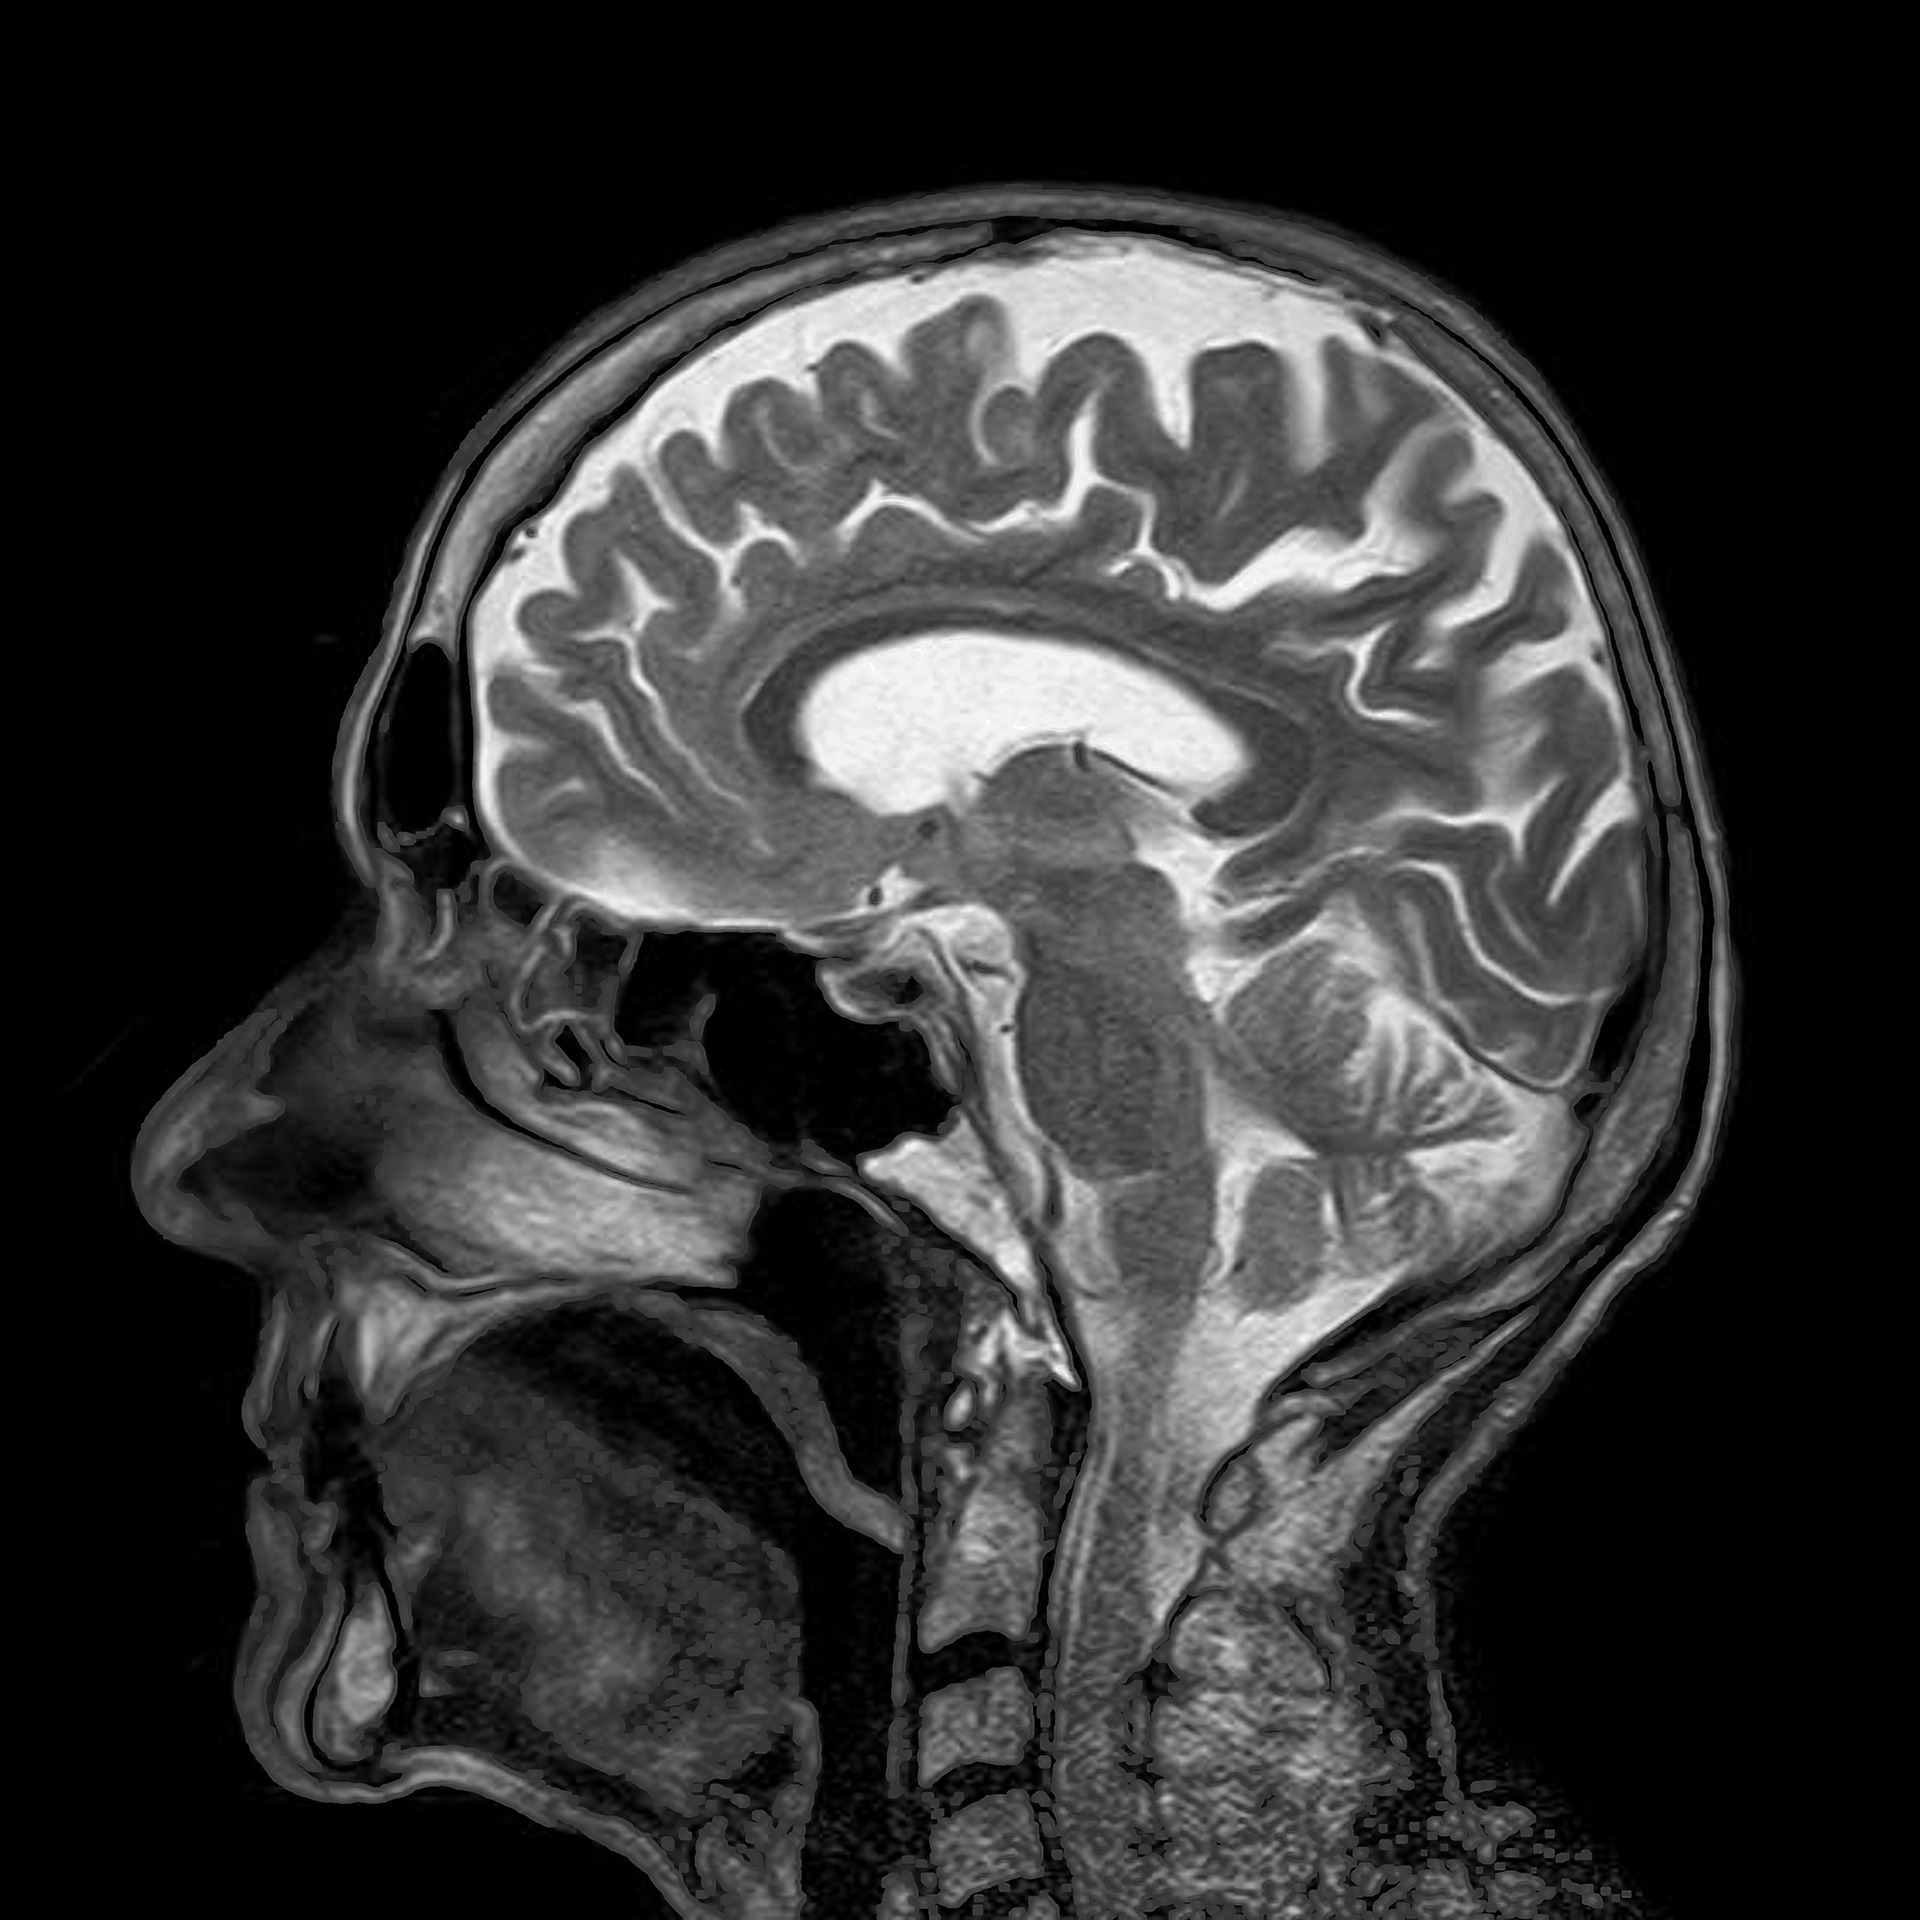

Does Mri Show Brain Death . Tonsilar herniation and loss of intraarterial flow signal voids (lifsv) on t2wi were highly sensitive and specific findings for the. No, people don’t recover from brain death. This can be assessed by a number of. Can mri detect brain damage?mri is particularly good at characterizing brain lesions. In the early 1990s, first. After an elderly patient died suddenly during a routine test, scientists accidentally captured unique data on the activity in his brain at the very end of his life: The advent of magnetic resonance imaging has improved diagnostic possibilities in brain death, due to several sophisticated techniques offered by mri. Brain death signifies the complete, irreversible cessation of brain function, including the capacity for the brainstem to regulate respiratory. Healthcare providers follow strict guidelines about. This helps distinguish between normal and. Different mri sequences provide clear contrasts. Does anyone ever recover from brain death? The brain mri features of brain death are parallel to the ct fi ndings, demonstrating the primary insult that led to brain death or secondary. During the 30 seconds before. Most imaging tests for brain death rely on the absence of cerebral blood flow as a surrogate for brain death.

Does Mri Show Brain Death Different mri sequences provide clear contrasts. Most imaging tests for brain death rely on the absence of cerebral blood flow as a surrogate for brain death. No, people don’t recover from brain death. Brain death signifies the complete, irreversible cessation of brain function, including the capacity for the brainstem to regulate respiratory. The advent of magnetic resonance imaging has improved diagnostic possibilities in brain death, due to several sophisticated techniques offered by mri. This can be assessed by a number of. During the 30 seconds before. The brain mri features of brain death are parallel to the ct fi ndings, demonstrating the primary insult that led to brain death or secondary. This helps distinguish between normal and. Does anyone ever recover from brain death? In the early 1990s, first. After an elderly patient died suddenly during a routine test, scientists accidentally captured unique data on the activity in his brain at the very end of his life: Different mri sequences provide clear contrasts. Healthcare providers follow strict guidelines about. Can mri detect brain damage?mri is particularly good at characterizing brain lesions. Tonsilar herniation and loss of intraarterial flow signal voids (lifsv) on t2wi were highly sensitive and specific findings for the.